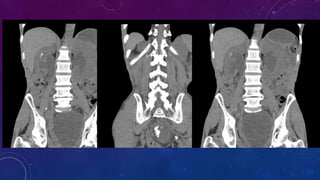

FAILED BILATERAL RENAL TRANSPLANTS

CALCIFICATION

• Failed kidney transplant

• Seminal vesicle / vas deferens calcification